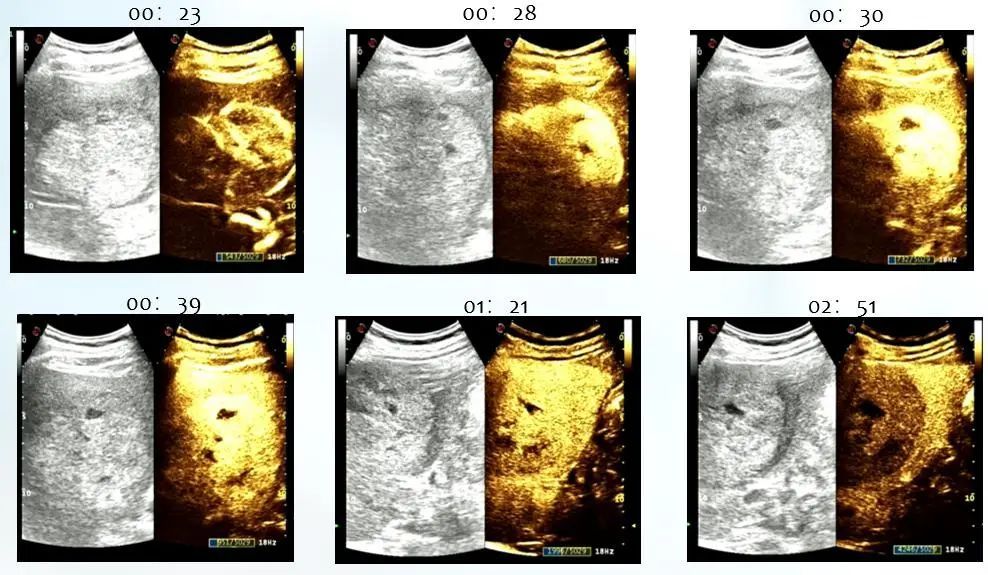

图2. 超声造影声像特征